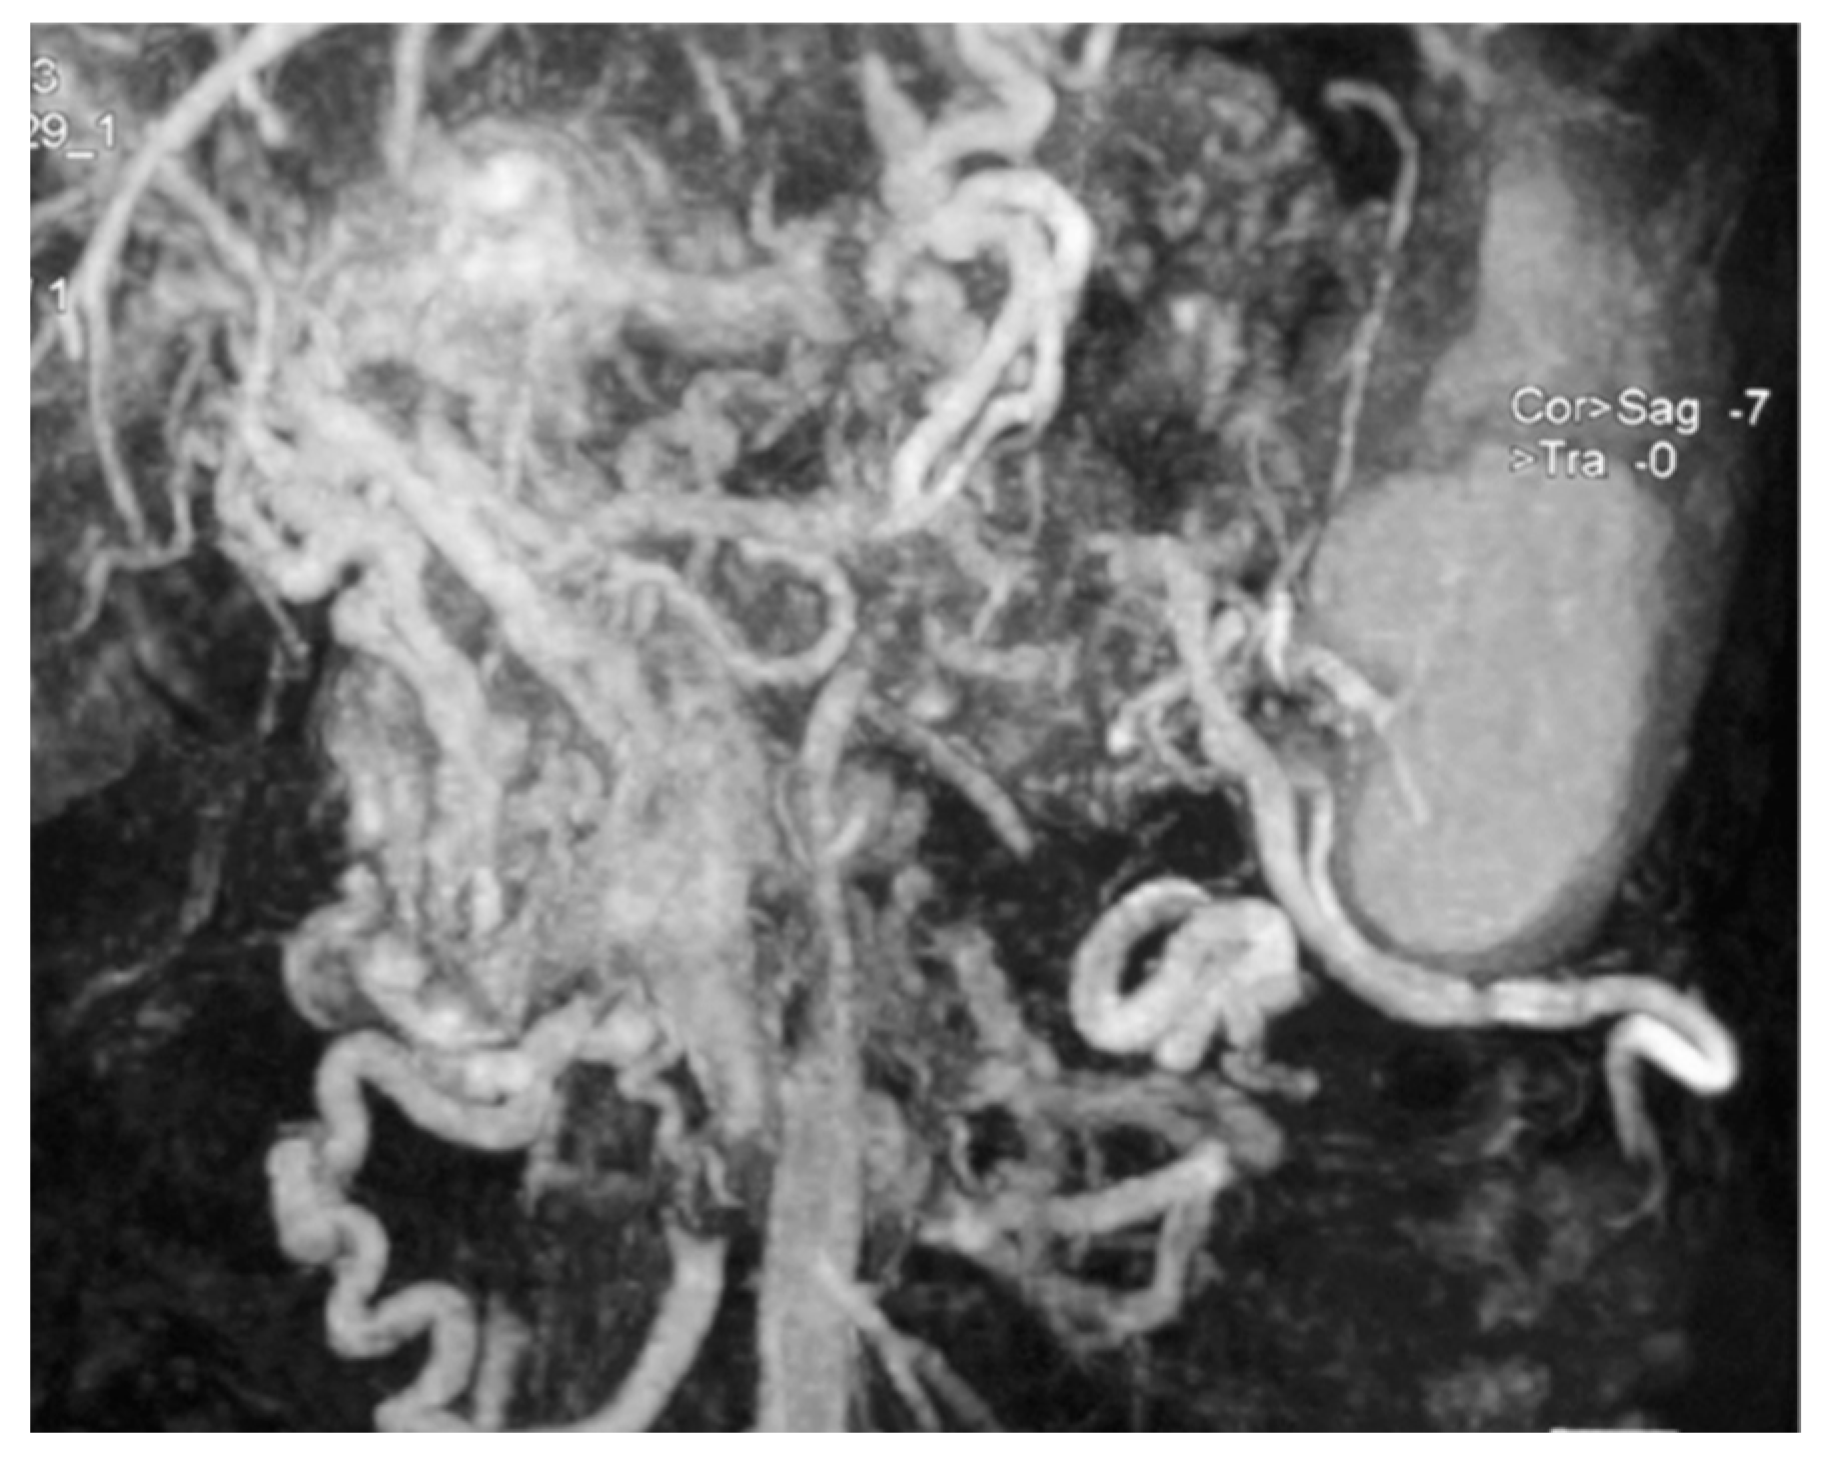

| 1 | Head 4.0 | Bilobar liver | Liver | T2 Nx M1 IV | NET n.a. | 5-HT 20–20–30% Grimelius | Insulin, Gastrin, PP | SS-A, CT a | 158 | DOD |

| 2 | Tail 2.5 | Bilobar liver | Liver | T2 Nx M1 IV | NET n.a. | CgA | n.a. | TACE | 12 | DOD |

| 3 | Body 4.0 | Bilobar liver, mediastinal LN | Liver | T2 N1 M1 IV | NET n.a. | CgA, Grimelius | n.a. | CT b | 29 | DOD |

| 4 | Tail 6.0 | Bilobar liver | Abdominal LN | T3 N1 M1 IV | NET 3.4% | CgA, Syn, NSE | 5-HT, Insulin, Gastrin, Glucagon, SS, PP, Calcitonin | SS-A, CT b, TAE, PRRT | 96 | DOD |

| 5 | Body 10.0 | Bilobar liver, cervical LN | Cervical LN | T4 N1 M1 IV | NEC n.a. | n.a. | n.a. | SS-A, CT c | 16 | DOD |

| 6 | Body 4.0 | Bilobar liver | Liver | T2 N1 M1 IV | NET 16% | CgA, Syn | n.a. | Biliary stent SS-A, CT d Liver MW Everolimus | 117 | AWD |

| 7 | Body 3.6 | Bilobar liver | Liver | T2 Nx M1 IV | NET 70% | 5-HT, CgA, Syn, Calcitonin | NSE, Insulin, Gastrin, Glucagon, SS, PP, VIP | CT e | 5 | DOD |